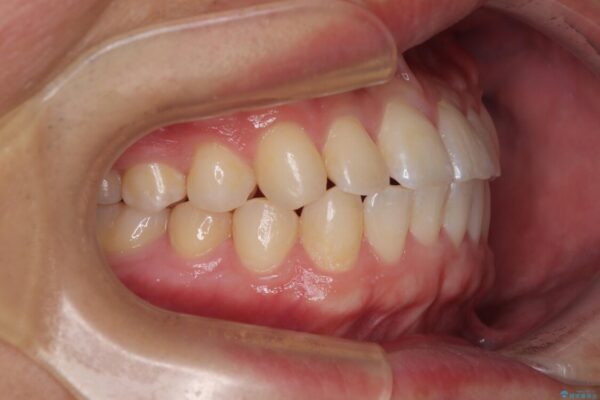

シザーズバイトの奥歯も正常なかみ合わせに改善

治療後

• 前歯のガタガタ・奥歯のかみ合わせ(シザーズバイト)を改善|1年半で完了したメタルブラケット矯正 治療後画像